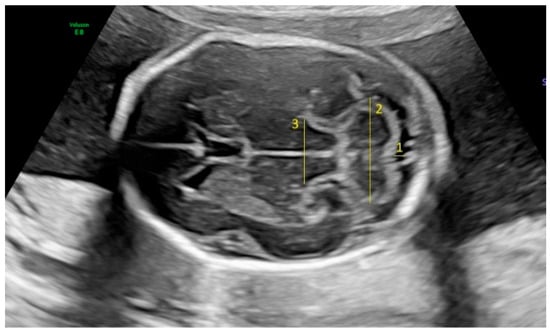

Fetal biometric parameters and fetal intracranial structures were assessed via ultrasonography. The following fetal intracranial measurements were included: posterior lateral ventricle (PLV), cavum septi pellucidum (CSP), thalamus, cisterna magna (CM), and transverse cerebellar diameter (TCD). Prenatal ultrasonographic examinations were performed using a Voluson E8 Expert system (GE Healthcare, Tiefenbach, Austria) equipped with a 2–9 MHz 2D curvilinear transducer. All ultrasound assessments were conducted once by the same perinatologist, following the guidelines of the International Society of Ultrasound in Obstetrics and Gynecology and the World Association of Perinatal Medicine [18,19]. The PLV was measured on an axial transventricular plane that displays the anterior and posterior horns of the lateral ventricles, at the level of the atrium, perpendicular to the long axis of the ventricle. Calipers were placed on the inner (echogenic) edges of the ventricle walls at the widest point (inner-to-inner measurement). The thalamus, cerebellum, and CM were visualized on a transcerebellar plane. The transverse thalamic diameter was measured between the widest points of the thalami. For the TCD, calipers were placed on the outer edges of the cerebellum. CM was measured as the greatest distance between the posterior edge of the cerebellar vermis and the inner surface of the occipital bone. CSP was assessed on both the transventricular and transcerebellar planes, with the measurement taken on the transventricular plane. CSP width was measured from inner edge to inner edge, perpendicular to the midline (Figure 1 and Figure 2).

Figure 1. Fetal intracranial structures in the transcerebellar plane (1: cisterna magna; 2: cerebellum; 3: thalamus).